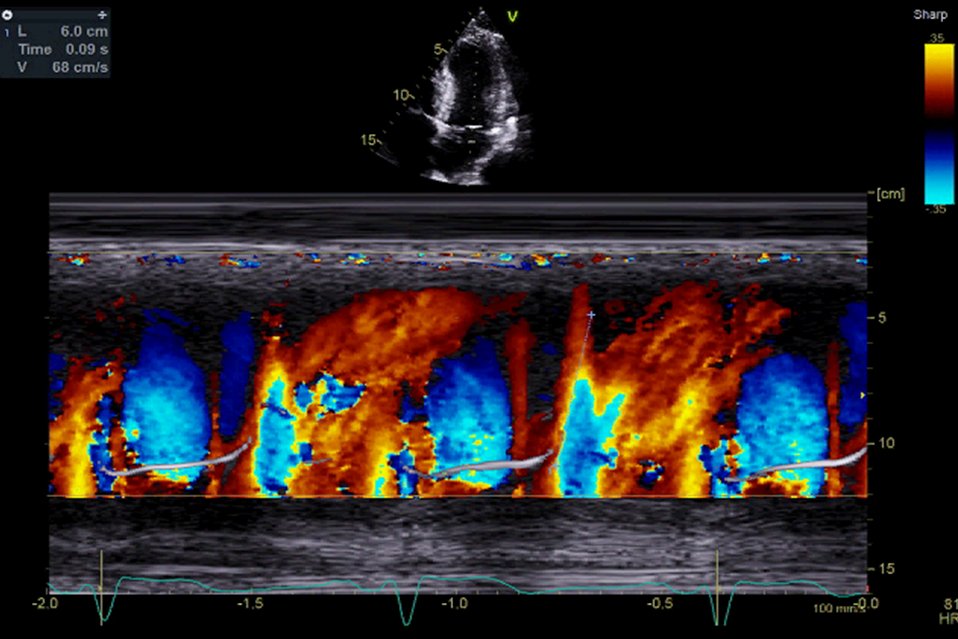

How many people use MV flow propagation velocity (Vp) routinely? The data suggest it's preload independent and a marker of diastolic dysfunction in AF. We use a cut-off of Vp <45cm/s to suggest impaired LV relaxation. #echofirst EchoTalk Echocardiography Echocardiography Echocardiography Katherine Collins MSc FBSE